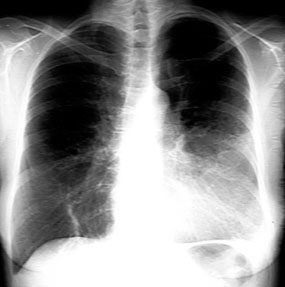

LUL Consolidation

-

The left heart border is obliterated with most of the left upper lung white with black branching density.

There is loss of aortic and left heart silhouette, indicating LUL disease (silhouette sign). Left

hemi diaphragm is clearly seen indicating normal lower lobe.

Branching black tubular density is the air bronchogram.

In the lateral view, the oblique fissure is in its normal location with density anterior to it corresponding to LUL (no loss of lung volume).